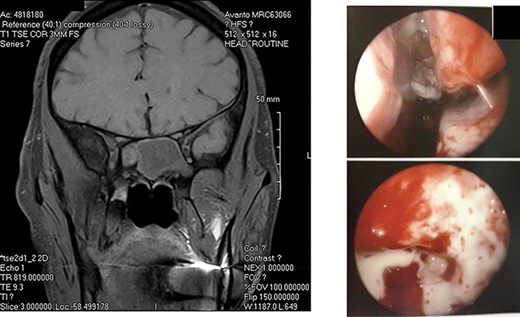

A: Magnetic resonance imaging (coronal view) reveals an expansile sphenoid sinus mass with fluid characteristics with extension into the cavernous sinus on the right. B: Intra-operative view through an endoscope reveals mucopurulent material from right sphenoid ostium. Sphenoid sinus reveals clumps of extramucosal ‘peanut buttery’ visco-elastic material (allergic mucin).

A diagnosis of right posterior cavernous sinus syndrome was made, and patient was subjected to imaging. CT scan revealed complete opacification of sphenoid sinus with bony erosion. MRI of brain revealed an expansile sphenoid sinus mass (with fluid characteristics on restricted diffusion) indicative of a pyo-mucocele (Fig. 2A). Complete blood counts were within normal limits and erythrocyte sedimentation rate was 95 mm/hour. Immunological work-up including serum anti-nuclear antibody, anti-cytoplasmic antibody and HIV were negative. Blood cultures were negative for bacteremia and fungemia. Patient was started on intravenous vancomycin, fluconazole and Decadron (Merck & Co., Inc., Whitehouse Station, NJ) was added after 48 hours. Five days after initiating treatment, no response was noted.

He was taken to the operating room, and an endoscopic exploration of sphenoid sinus was performed through sphenoethmoid recess. There was mucopurulent material drained through sphenoid ostium, and clumps of extramucosal ‘peanut buttery’ visco-elastic material (allergic mucin) were found in sphenoid sinus intra-operatively (Fig. 2B). One month post-operatively, patient’s visual acuity was 20/20, and extraocular movements revealed a minimal right abduction deficit.

Diagnosis of AFS is based on history of type I hypersensitivity, presence of nasal polyposis, characteristic CT and MRI findings, presence of ‘allergic fungal mucin’ intra-operatively and staining for fungal hyphae on histopathology [4]. MRI findings (T1 central hypointensity and T2 central signal void) when combined with CT is highly specific [1]. However, histopathology can be inconclusive as yield is variable [5]. Diagnosis in our patient was based on the characteristic imaging and intra-operative findings.